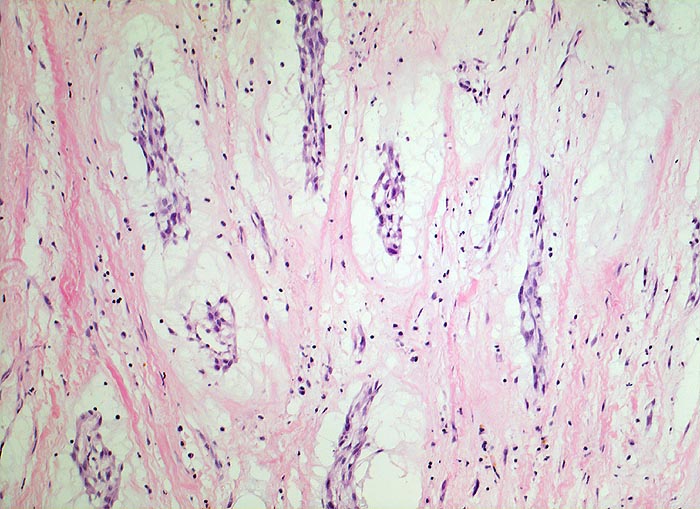

Vorhofmyxom

benigner Tumor

Herz Vorhof

Kardiovaskuläres System

Beschreibung

Histologie

100